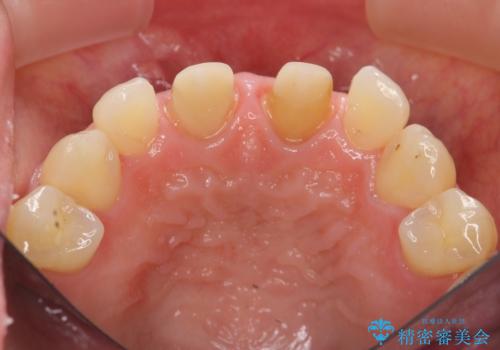

短期集中 前歯審美治療

- 3週間後に迫った結婚式までになんとか前歯をきれいにしたいという希望で来院されました。

一回の治療時間を長く取り、限られた時間で最大限の結果を出せるよう集中治療を計画します。

ただ見えるクラウンを白くきれいにするのではなく、長期的な歯の予後を考えると根管治療・ファイバーコア築盛・精密な歯牙形成等クリアすべき条件は多々あると言えます。